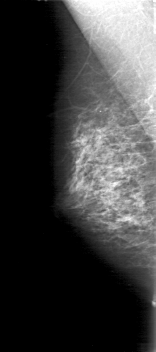

D_4038_1.LEFT_CC

LEFT_CC LINES 5041 PIXELS_PER_LINE 2056 BITS_PER_PIXEL 12 RESOLUTION 43.5 OVERLAY

FILE: D_4038_1.LEFT_CC.OVERLAY

TOTAL_ABNORMALITIES 1

ABNORMALITY 1

LESION_TYPE MASS SHAPE OVAL MARGINS OBSCURED

ASSESSMENT 0

SUBTLETY 4

PATHOLOGY BENIGN

TOTAL_OUTLINES 1

BOUNDARY